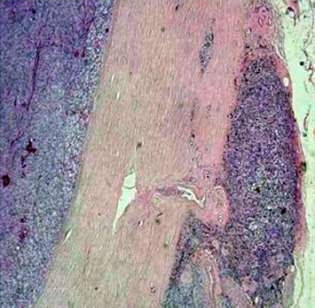

"MR microscopy visualizes the eye and its surrounding lipid tissue. This permits us to ascertain whether a tumor is growing into the surrounding tissue or not, which can play a decisive role in designing a therapy," he noted at the meeting. "Histological interpretation of the tumors produced, for all cases, identical results as in MR microscopy. For example, pathologists established that two tumors had grown into the surrounding tissue, congruent with our previous diagnosis based on MR microscopy."

To improve the quality and consistency of the new technology, histopathologic validation of imaging findings is required. Correlation between microMR images and histopathology can provide a better understanding of malignant eye processes and their treatment, he stated.